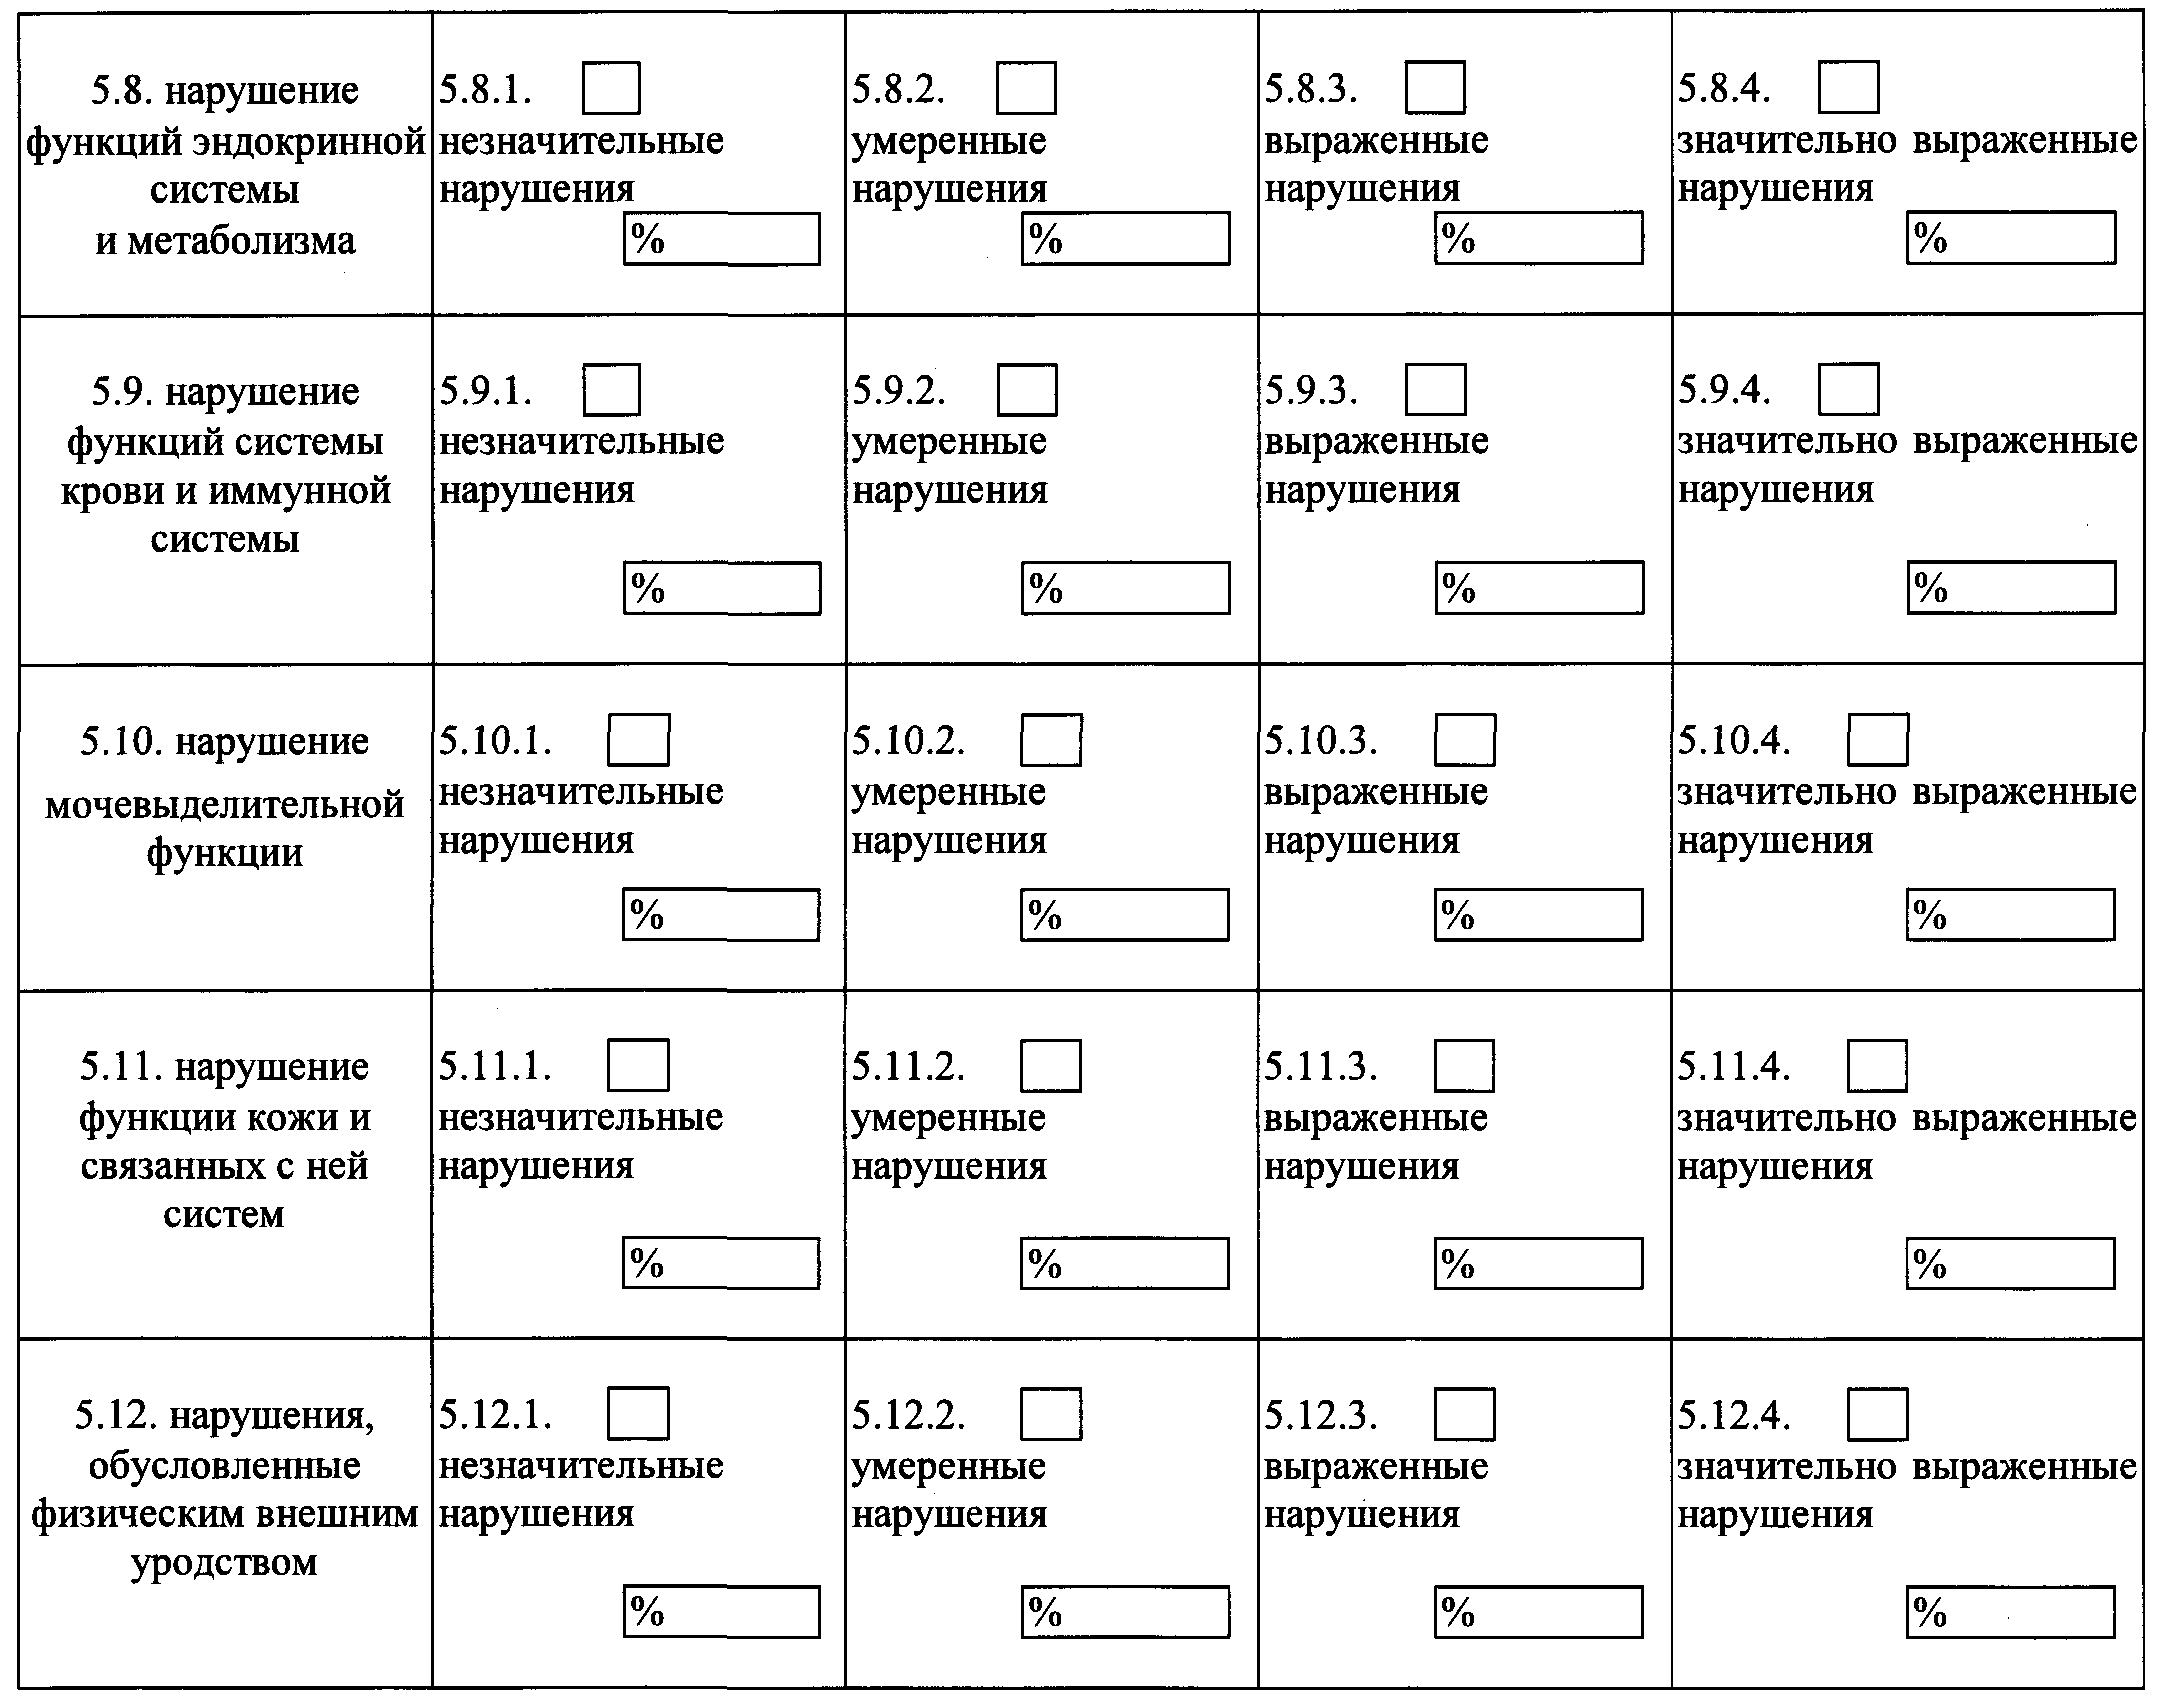

| ________________________________________________________________________ (наименование федерального государственного учреждения медико-социальной экспертизы и его адрес) 1. Фамилия, имя, отчество (при наличии) гражданина _____________________ ________________________________________________________________________ 2. Дата освидетельствования (день, месяц, год): «__» ___________ ____ г. 3. Акт медико-социальной экспертизы гражданина № ________________________ 4. Диагноз федерального государственного учреждения медико-социальной экспертизы: 4.1. основное заболевание: _____________________________________________ ________________________________________________________________________ ________________________________________________________________________ ________________________________________________________________________ 4.2. код основного заболевания по МКБ1: ________________________________________________________________________ 4.3. осложнения основного заболевания: ________________________________________________________________________ ________________________________________________________________________ ________________________________________________________________________ 4.4. сопутствующие заболевания: _________________________________________ ________________________________________________________________________ ________________________________________________________________________ ________________________________________________________________________ 4.5. коды сопутствующих заболеваний по МКБ: ____________________________ ________________________________________________________________________ 4.6. осложнения сопутствующих заболеваний: _____________________________ ________________________________________________________________________ ________________________________________________________________________ ________________________________________________________________________ 5. Виды стойких расстройств функций организма и степень их выраженности (согласно классификациям и критериям, используемым при осуществлении медико-социальной экспертизы граждан федеральными государственными учреждениями медико-социальной экспертизы, утвержденным приказом Министерства труда и социальной защиты Российской Федерации от 17 декабря 2015 г. № 1024н (зарегистрирован Министерством юстиции Российской Федерации 20 января 2016 г., регистрационный № 40650), с изменениями, внесенными приказом Министерства труда и социальной защиты Российской Федерации от 5 июля 2016 г. № 346н (зарегистрирован Министерством юстиции Российской Федерации 28 июля 2016 г., регистрационный № 43018): |

6. Ограничения основных категорий жизнедеятельности человека и степень их выраженности: